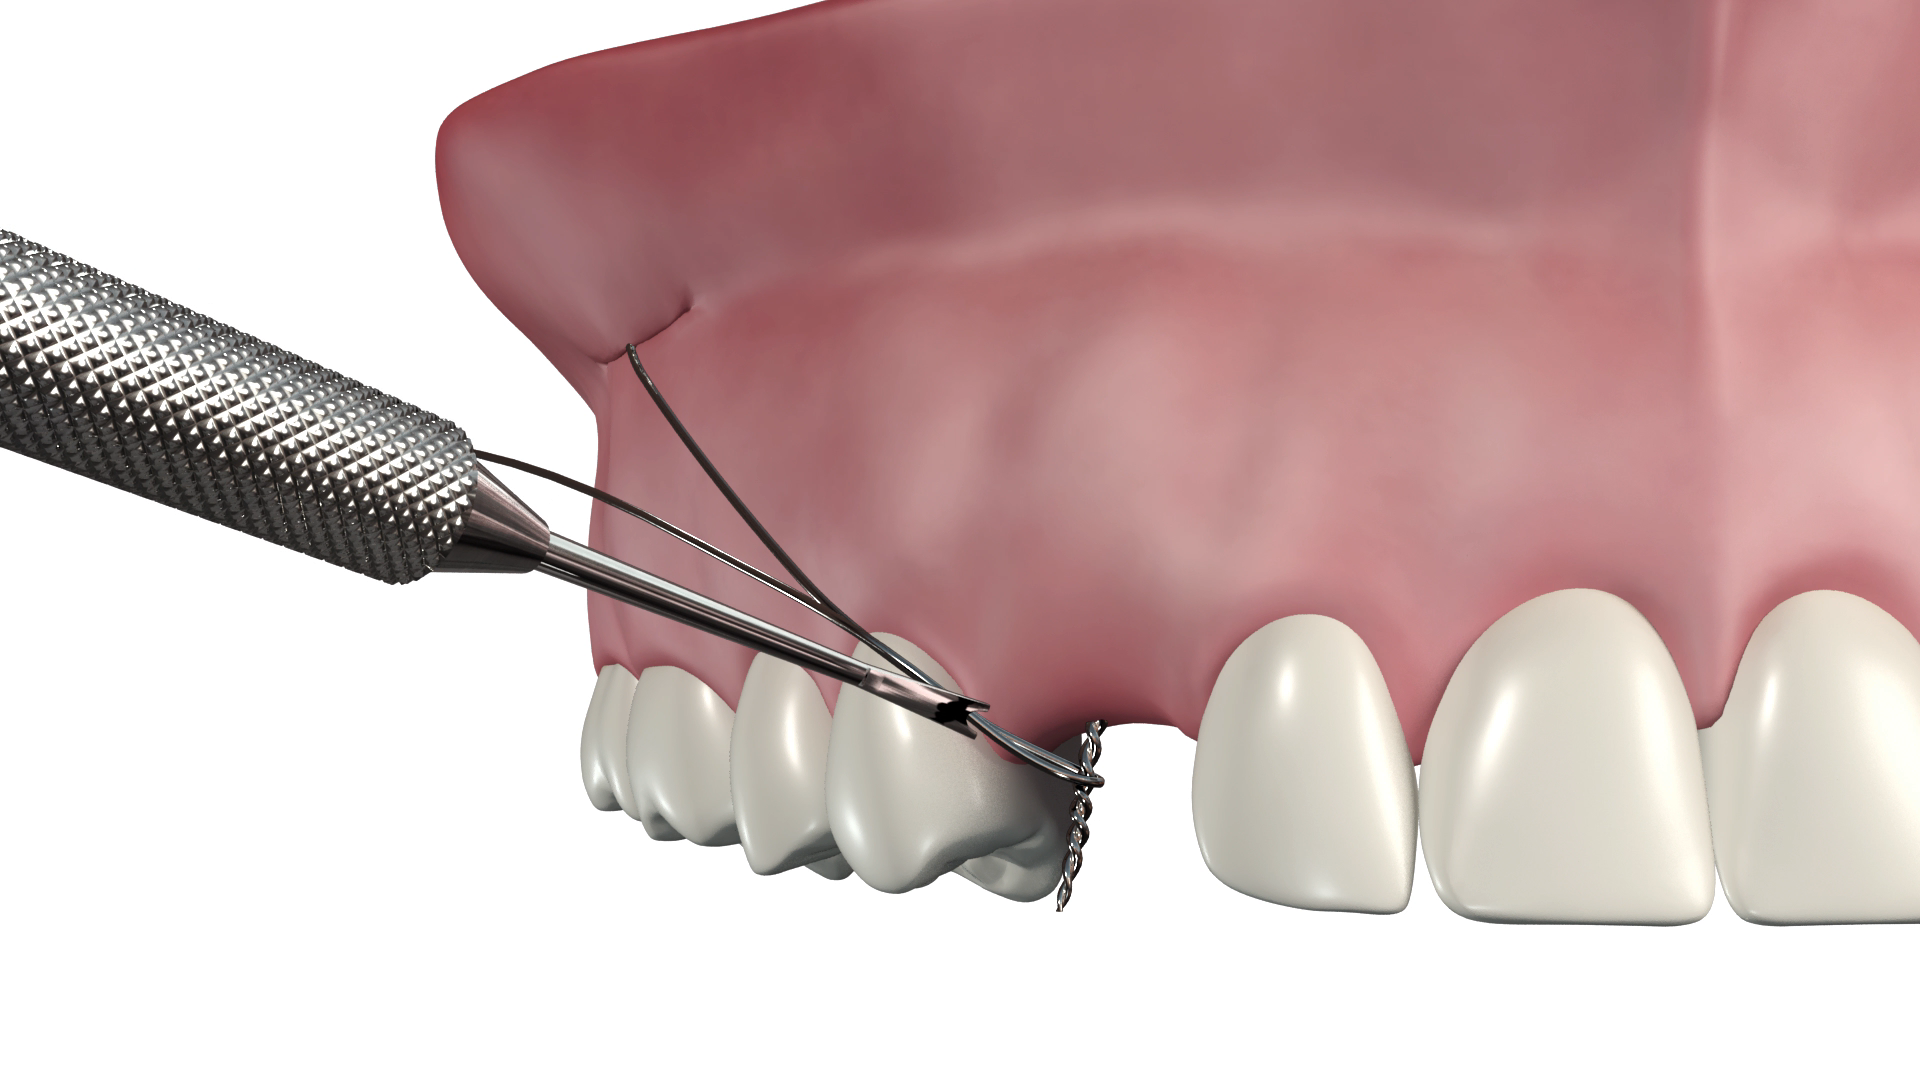

- Traction et mise en place des canines incluses

- La traction et la mise en place des canines incluses mandibulaires